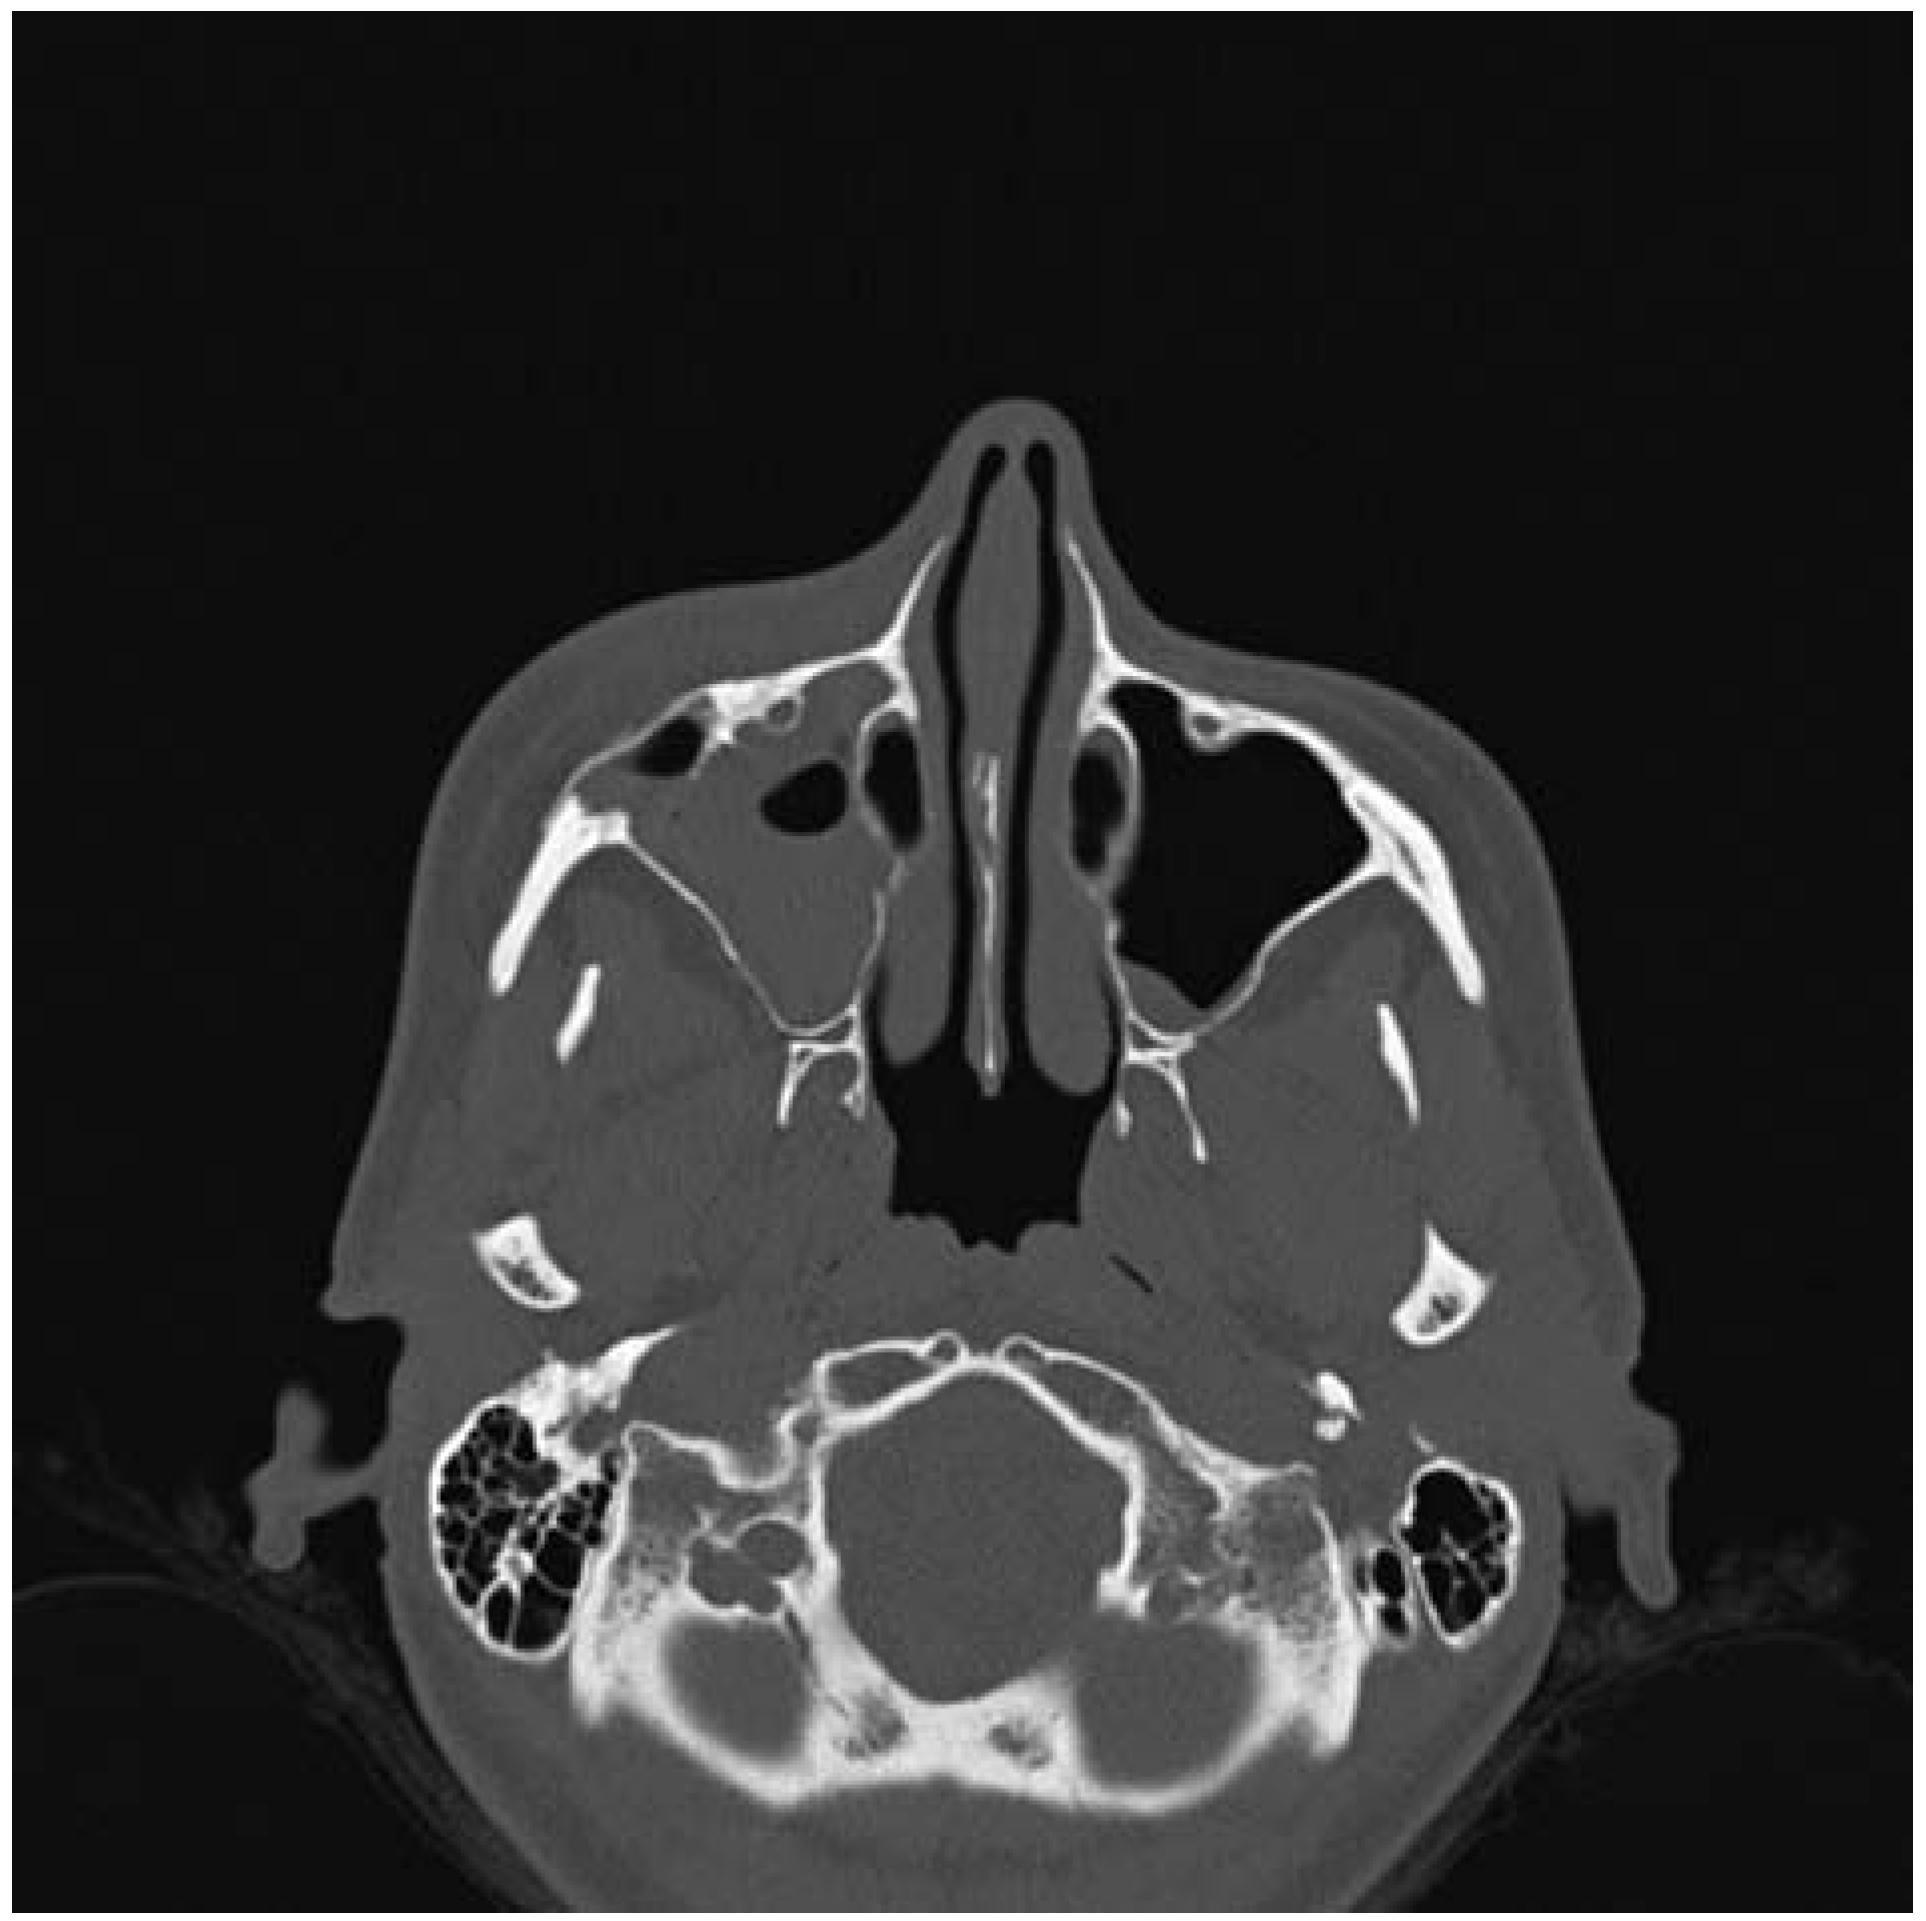

- Moore, S.L.; Chun, J.K.; Mitre, S.A.; Som, P.M. Intraosseous hemangioma of the zygoma: CT and MR findings. AJNR Am J Neuroradiol 2001, 22, 1383–1385. [Google Scholar] [PubMed]

- Razek, A.A. Imaging appearance of bone tumors of the maxillofacial region. World J Radiol 2011, 3, 125–134. [Google Scholar] [PubMed]

- Gonçalves, F.G.; Rojas, J.P.; Hanagandi, P.B.; et al. Case report: Periorbital intraosseous hemangiomas. Indian J Radiol Imaging 2011, 21, 287–290. [Google Scholar]